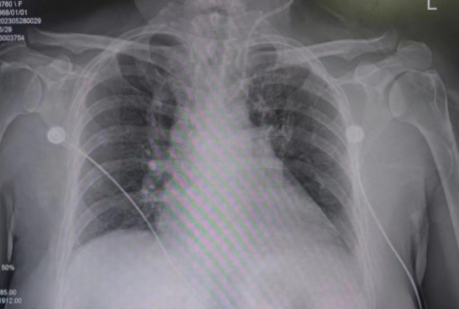

术后检查

因患者心功能极差,缺血再灌注损伤明显,术后第一天多次出现恶性心律失常,病情持续危重。在吉心ICU医生的严密监护下,患者各项生命体征逐渐好转,术后两天脱离IABP,术后三天脱离呼吸机,复查彩超心功能明显好转,患者转危为安,获得第二次生命。